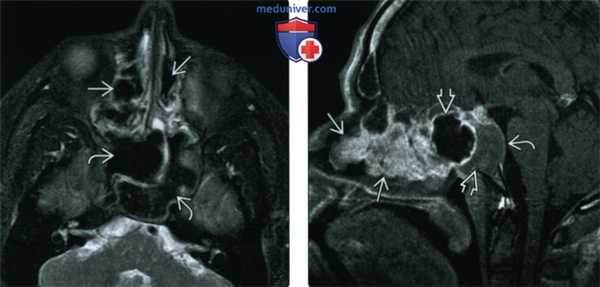

(Слева) При аксиальной МРТ Т2ВИ FS визуализируются гипоинтенсивные полипы, заполняющие решетчатые и основные пазухи и приводящие к их вздутию. На Т2 ВИ гипоинтенсивные полипы имитируют газ в пазухах.

(Справа) При сагиттальной МРТ Т1ВИ С+ у этого же пациента в полости носа визуализируются множественные полипы, накапливающие контраст. Полипы в основной пазухе характеризуются сигналом смешанной интенсивности. Обратите внимание на выраженное истончение кортикального слоя ската.

(Слева) При корональной «костной» КТ определяется снижение пневматизации левой верхнечелюстной пазухи, устье которой расширено. Визуализируется большой одиночный полип, пролабирующий через устье в полость носа и приводящий к обструкции среднего носового хода.

(Справа) При сагиттальной МРТ Т1 визуализируется крупный полип ва с промежуточным сигналом, пролабирующий из полости носа в носоглотку. Обратите внимание на нормальный гиперинтенсивный сигнал в небе ниже полипа. Ткань аденоидов слегка гиперинтенсивна по сравнению с полипом.